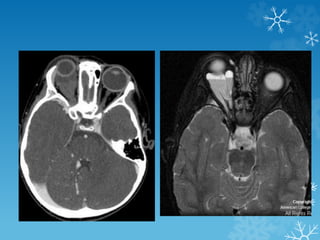

44 yrs. female – immunocompromised with altered mental status

44 yrs. female– immunocompromised with altered mental status